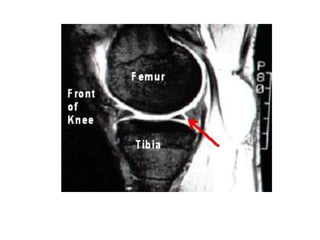

Torn meniscus on MRI (left) and during arthroscopy (right)

Torn meniscus onMRI (left) and during arthroscopy (right)

• #27 The double PCL sign appears on sagittal MRI images of the knee when there is a bucket-handle tear of the meniscus